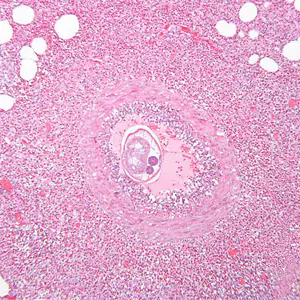

The clinical manifestations of abdominal angiostrongyliasis (A. costaricensis infection) arise from the parasite’s invasion of the gastrointestinal wall, and may mimic those of other conditions, such as appendicitis, Crohn’s disease, or Meckel’s diverticulum. Eosinophilia is commonly noted. Intestinal obstruction, perforation, and other complications may occur, as may ectopic infection (e.g., in the liver).

In humans, Angiostrongylus eggs and larvae remain sequestered in tissues and do not appear to be excreted in stool. A. costaricensis infections are predominantly abdominal; both eggs and larvae (occasionally adult worms) can be identified in biopsy or surgical specimens of intestinal tissue, where the eggs and larvae typically are engulfed in giant cells and/or granulomas.

The larvae of A. costaricensis in tissue sections need to be distinguished from larvae of Strongyloides . A. costaricensis first-stage (L1) larvae tend to be slightly smaller in diameter than S. stercoralis third-stage (L3) larvae and have single lateral alae, whereas S. stercoraliss L3 larvae have minute double lateral alae. The alae can be difficult to discern in most histologic sections. However, the presence of granulomas containing thin-shelled eggs and/or larvae generally serves to distinguish A. costaricensis infections from Strongyloides infections.